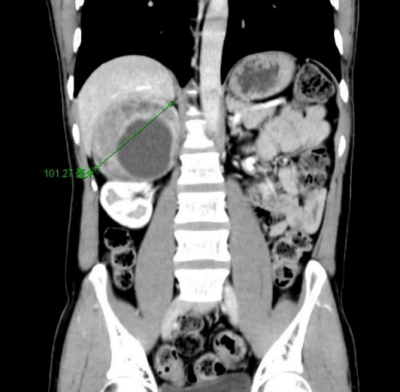

40岁的汤先生(化名)来自湖南娄底,近1年反复头晕、心悸,测血压经常高于180/110mmHg(标准血压收缩压<120mmHg、舒张压<80mmHg),有时高达230/120mmHg,长期使用降压药物却一直难以控制。经当地医院推荐,到91短视频 就诊,CT检查后发现他右侧肾上腺有一个10cm*8cm巨大肿瘤。泌尿外科二区主任、主任医师刘玉明结合症状及CT影像结果,考虑为嗜铬细胞瘤。由于肿瘤体积巨大,与周围十二指肠、下腔静脉粘连紧密,需紧急手术治疗。

图1:CT示右侧肾上腺巨大肿瘤